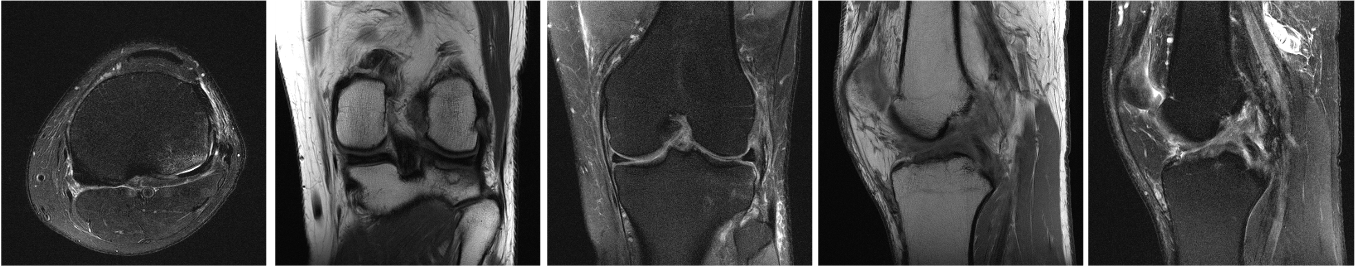

Image 2. MRI images from a typical clinical knee protocol, showing the knee in different orientations and with different image contrasts, created depending on the acquisition settings of the MRI scanner. Courtesy of Florian Knoll.